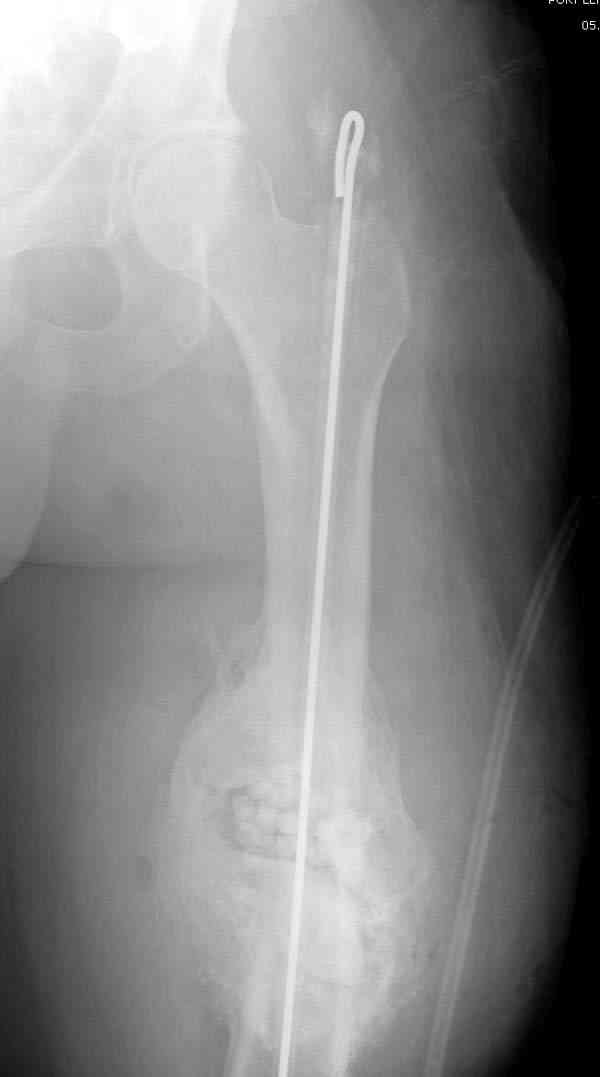

Этот стиль мне полностью приемлем и понятен. Наверно я бы поступил также. Но статистика упрямая вещь. Сколько у тебя или у другого врача опыта по замещению дефектов бедра? У меня за 25 лет работы 3, и еще около 15 случаев удлинения бедра. Случай у тебя очень сложный. Если Вы выбираете Илизаровскую методику то надо на в/з хорошую дугу, не менее 4-5 спиц с напайками.Стержни хороши когда кость не измучена и на 2-4 месяца. Здесь аппарат на 6-8 месяцев. Если есть желание я только за, и

желаю только успеха и чтоб все трудности которые будут преодолел.

Прикрепляю пример замещения дефекта бедра 20 см, после резекции по поводу опухоли, эндопротеза Сиваша, вялотекущего остеомиелита со свищами в течении 3 лет. Получилось хорошо и всего за 6 месяцев в аппарате. Колена не было. У Вас случай сложнее. Это было в 1998г. Я работал в ЦИТО и у меня было 4 больных, я занимался им с утра до ночи. Сейчас 60 больных и операций в нашем отделении 25-30 в неделю.Если могу чем помочь - нет проблем.